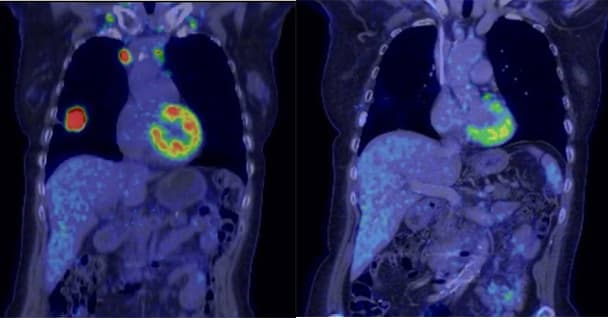

Bildtext: PET/DT-bilder på samma patient, till vänster före och till höger efter cancerbehandling. Man ser tydligt hur lungtumören "lyser upp" samt lymfkörtlar.